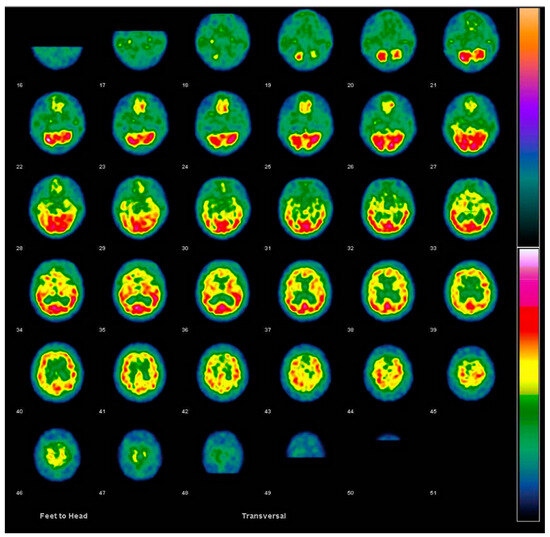

6.1.1. Imaging Data Display [45,50]

| FDG PET |

|